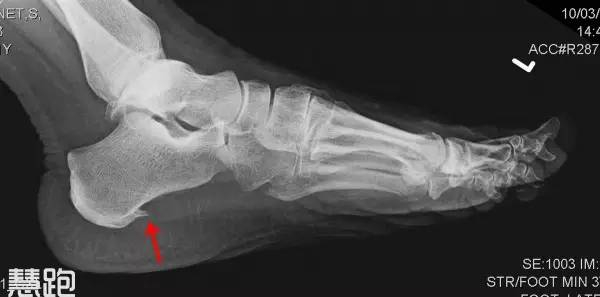

有跑友到医院检查,拍片后显示有跟骨骨刺(专业术语称为跟骨骨赘),大惊失色,会认为足底长出骨刺自然戳着疼。其实,骨刺不是导致疼痛的主要原因,骨刺刺激了足底筋膜才是产生疼痛的主要原因,足底筋膜炎治好了,自然疼痛也就消失了,所以对于跟骨骨刺不必过度担心。